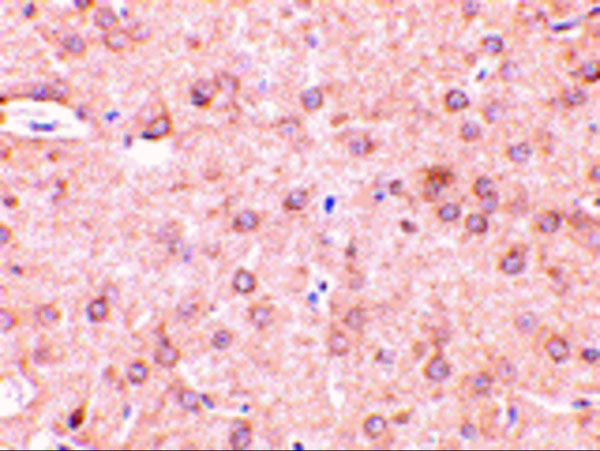

BCL-2, Monoclonal Antibody (Cat# AAA30284)

BCL-2, Monoclonal Antibody (Cat# AAA30003)